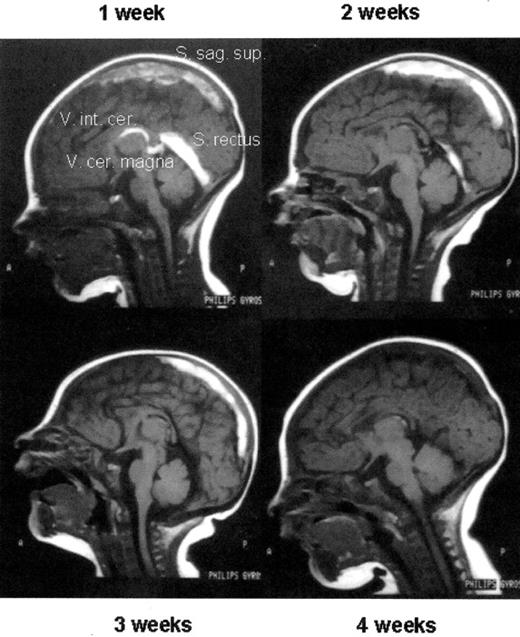

ADAMTS13

ADAMTS13 regulates the size of VWF multimers and thereby its functional activity in primary hemostasis. Its deficiency has clearly been assessed as playing the causative role in TTP.26 An acquired form, caused by autoantibodies against ADAMTS13, and an inherited form called Upshaw Schulman syndrome (USS) due to mutations in the gene, exist. Lack of the protease correlates with persistence of supra large VWF multimers (Figure 1 ) and, on an adequate trigger (infection, stress, hypoxia), these large multimers will induce platelet adhesion and aggregation in the microcirculation with subsequent microangiopathy, finally resulting in organ failure and death in 80% of cases when untreated. Thrombosis of larger venous and arterial vessels has also been observed. In childhood, TTP is rare and seems more often inherited.29 Oligo-symptomatic courses have been observed, however, their long-term prognosis is not clear. In addition to the obvious causative role of severe ADAMTS13 deficiency in TTP, the impact of milder ADAMTS13 deficiency as thrombophilic factor has not been assessed yet, but is subject of ongoing studies. ADAMTS13 has been identified as a potent antithrombotic in an animal model,30 which may be of future therapeutic interest.

Supra large VWF multimers in 3 siblings (thrombotic thrombocytopenic purpura [TTP]) with hereditary ADAMTS13 deficiency compared to normal plasma (NP). Activation of ADAMTS13 in normal plasma (NP +a) results in complete proteolytic cleavage of VWF multimers, whereas VWF in the TTP patient (TTP +a) remains unchanged due to the lack of ADAMTS13.